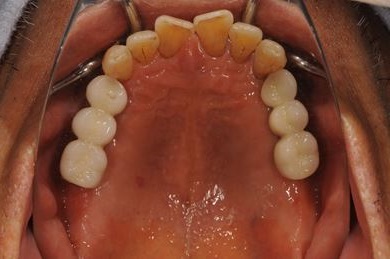

インプラントの症例写真 IMPLANT

骨再生スピードインプラント治療

| 主訴 | 欠損部分のインプラント・差し歯治療を希望。 | ||||||||||||||||||||||||||||||||

| 治療方針 | サイナスリフト、ソケットリフトによりインプラント治療を可能にする。抜歯と同時にインプラントを埋入し、治療期間を短縮する。 | ||||||||||||||||||||||||||||||||

| 治療内容 | インプラント8本(サイナスリフト、ソケットリフト、GBR)、メタルボンドセラミック8本 | ||||||||||||||||||||||||||||||||

| 総治療費 | 3,711,540円 | ||||||||||||||||||||||||||||||||